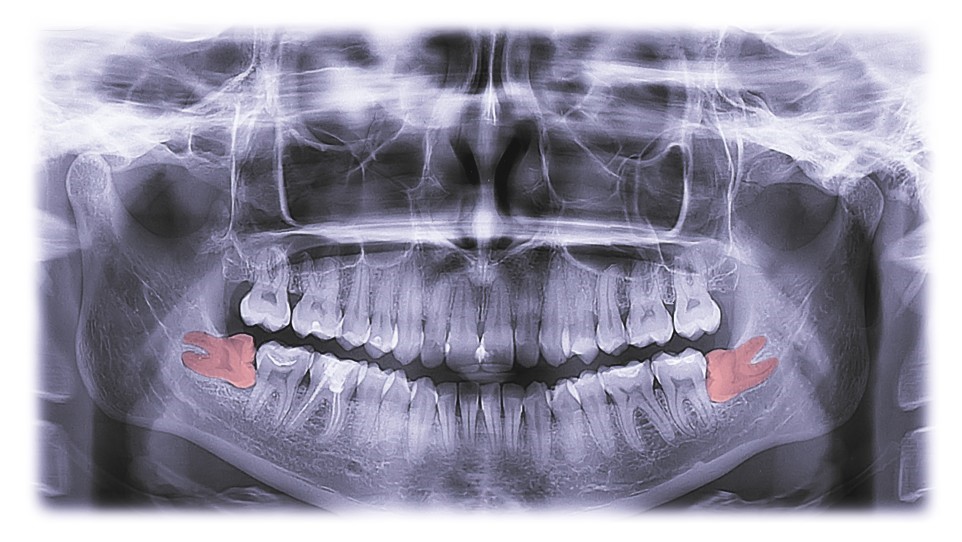

An OPG Showing Impacted lower Right And Left Wisdom Teeth

Wisdom teeth, also known as third molars, typically emerge between the ages of 17 and 25. While some individuals experience no issues with their wisdom teeth, others may face various complications that necessitate their removal. Here’s an overview of wisdom teeth removal, including the reasons for extraction, the procedure, and post-operative care.

1. Impaction: Wisdom teeth often become impacted, meaning they don't have enough space to emerge or grow properly. This can lead to pain, infection, and damage to adjacent teeth.